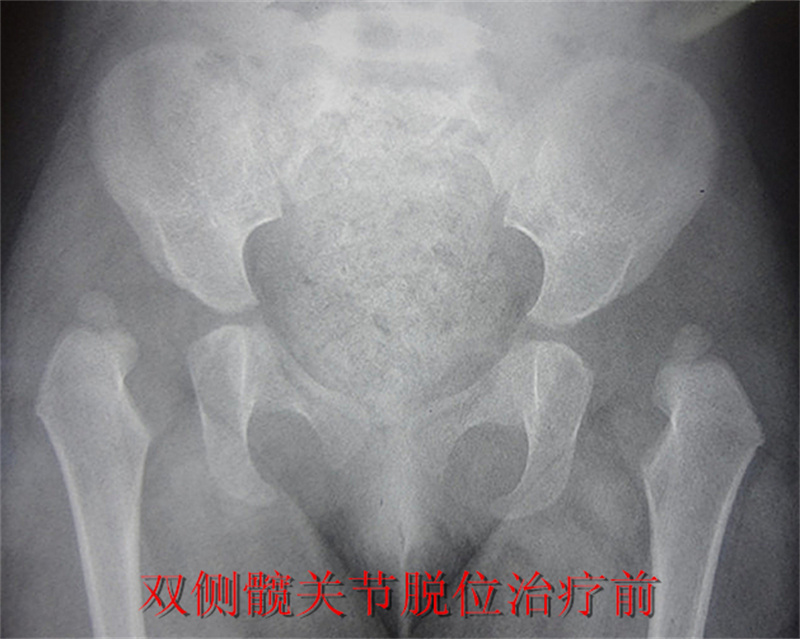

发育性髋关节的脱位的诊断与治疗注重一个“早”字,即早发现、早诊断、早治疗。如何做到早发现、早诊断呢。主要是对存在高危因素的孩子早筛查。一般来说发育性髋关节脱位在女孩多见,第一胎多见,怀孕时胎位为臀位的为高危因素,尤其是家族中有髋关节脱位病史的要高度关注,如出生后发现孩子双下肢不等长,臀纹不对称(见图1),关节有弹响,双髋展不开,或合并有“斜颈,马蹄内翻足”等畸形的应及早来儿童医院骨科进行筛查。对能独立行走的孩子,如出现无痛性的跛行,或走路较同龄孩子晚,均应到儿童医院骨科就诊。筛查的手段除常规的询问病史,查体外,还要进行影像学检查。对小于4月龄的孩子,行髋关节B超检查,4月龄以上的孩子,需进行骨盆平片(图2)的检查。对诊断明确的患儿,要及早进行治疗,治疗越早,方法越简单,创伤越小,效果越好。一般来说:对≤6月龄的孩子,是治疗的黄金阶段,多采用保守治疗的方式,如支具治疗;6-18月的患儿多采用闭合

复位石膏或支具固定,部分闭合复位不能成功的,需切开复位;18月-36月的多采用手术治疗,如切开复位,骨盆及股骨截骨治疗等;对于年龄更大的孩子,治疗方法更为复杂,影响远期效果。